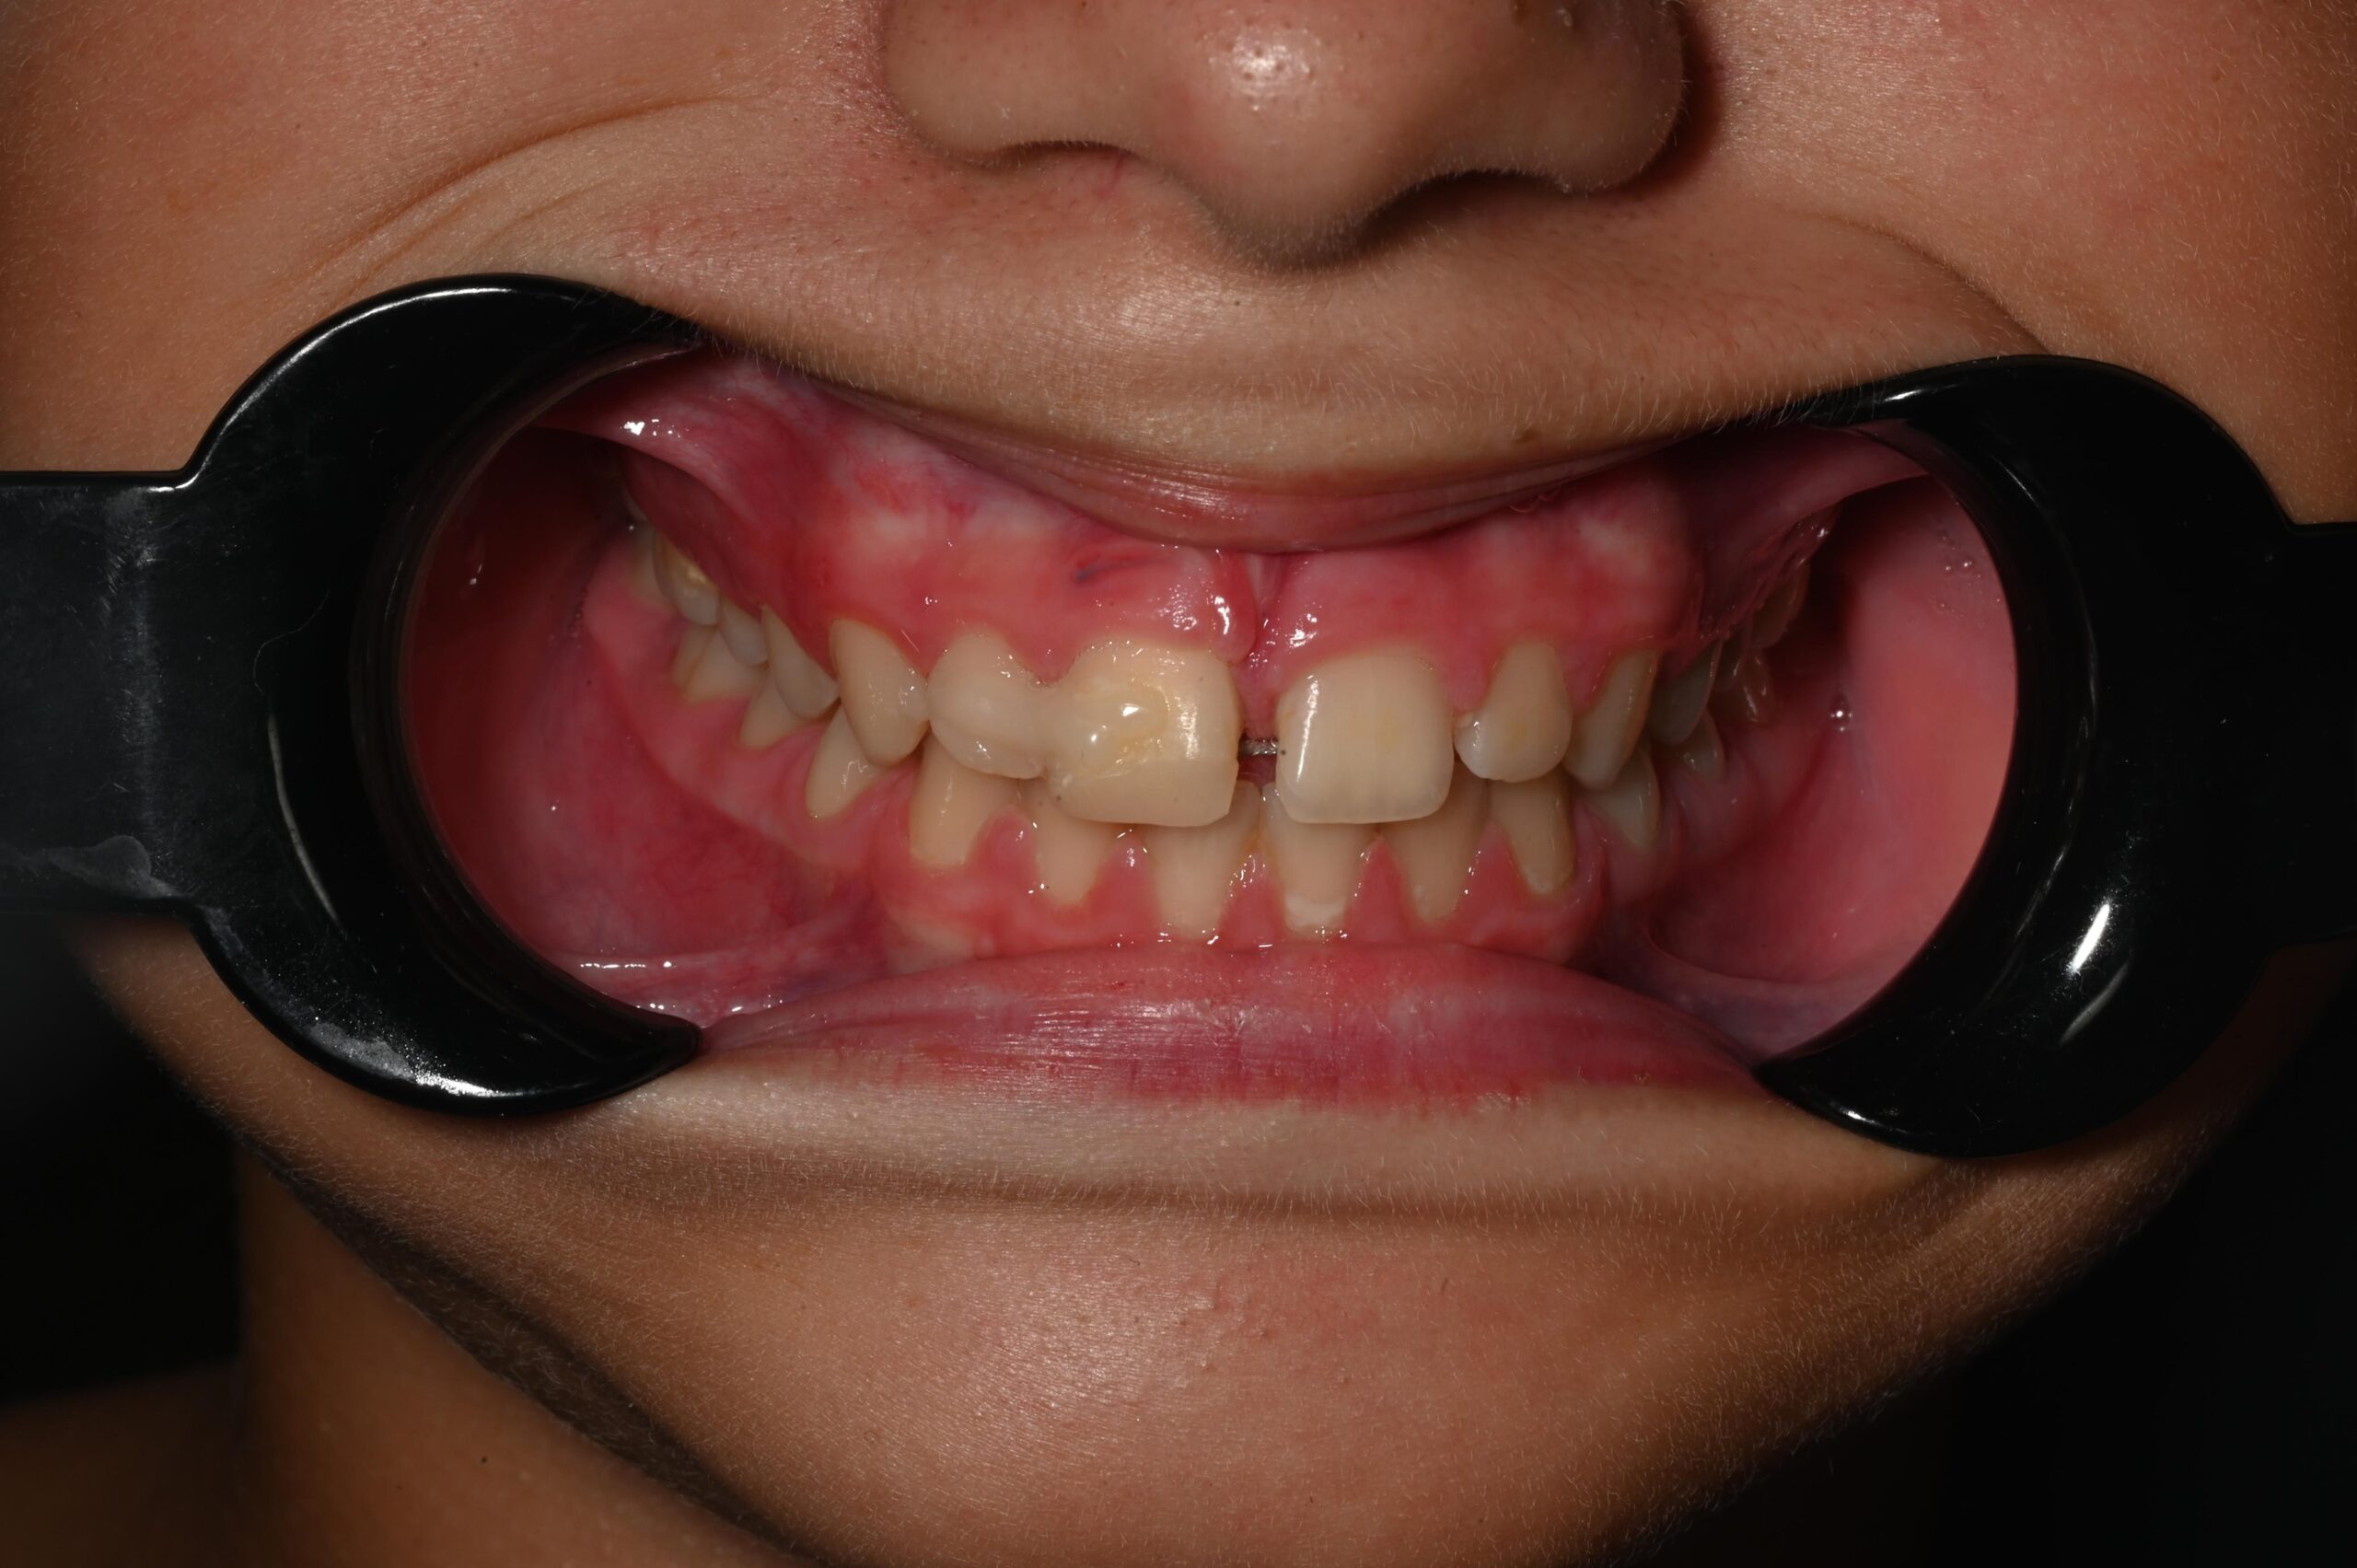

3. Splintimi stabilizues – kombinim i kompozitit dhe telit ortodontik

U përdor një teknikë e kombinuar splintimi:

• Kompozit në anën vestibulare, i cili jep fleksibilitet dhe estetikë.

• Tel ortodontik në anën palatinale, i cili përforcon stabilitetin pa e ngurtësuar dhëmbin në mënyrë të tepruar.

Ky lloj splintimi i “butë” (flexible splint) është i rekomanduar në trauma të këtij lloji, sepse ndihmon në rigjenerimin e ligamentit periodontal.

7. Kontrolli pas 24 orësh

Pacientja u rikthye për kontroll të menjëhershëm. Në ekzaminim u vu re:

• mungesë dhimbjeje,

• stabilitet i dhëmbit,

• inde të qeta pa inflamacion,

• mungesë komplikacionesh akute.

Kjo vizitë e parë është një ndër indikatorët më të fortë të ecurisë pozitive të shërimit.